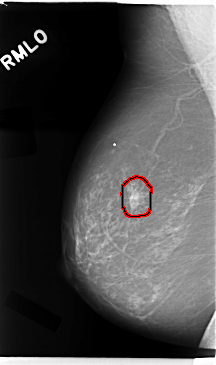

C_0016_1.RIGHT_MLO

FILE: C_0016_1.RIGHT_MLO.OVERLAY

TOTAL_ABNORMALITIES 1

ABNORMALITY 1

LESION_TYPE MASS SHAPE IRREGULAR MARGINS SPICULATED

ASSESSMENT 5

SUBTLETY 5

PATHOLOGY MALIGNANT

TOTAL_OUTLINES 1

BOUNDARY